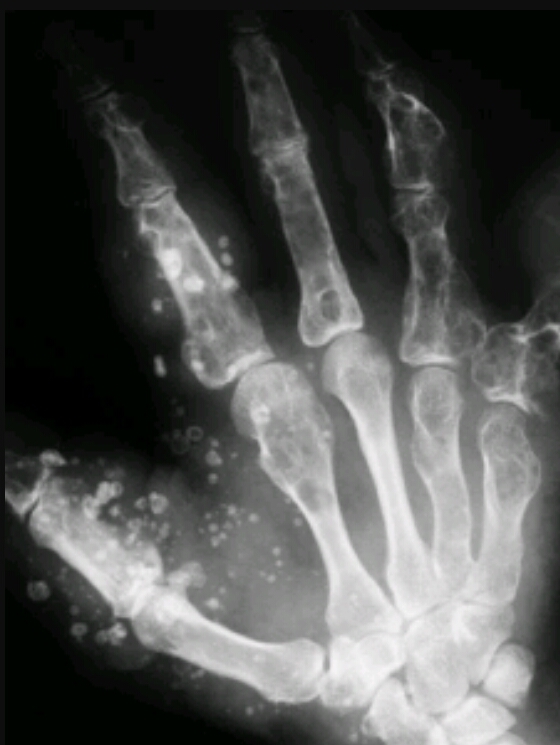

Findings? Diagnosis?

Multiple enchondromas

Ollier’s disease

Diagnosis?

Maffucci syndrome